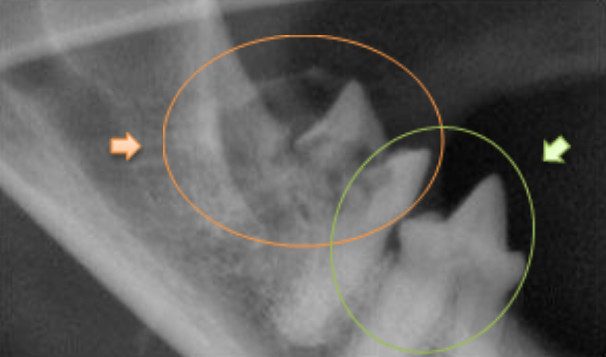

Below: The same tooth showing extensive destruction of both the tooth root and crown (the part above the gum line). This shows on the X-ray as grey fluffy looking areas (highlighted by the orange arrow and circle), compare this to the adjacent healthy tooth root and crown showing on the X-ray as a solid white tooth (highlighted by the green arrow and circle). This is a feline resorptive lesion and is a very painful condition. (Image reproduced with kind permission from Dr Tara Cashman, President of the Australian Veterinary Dental Society), demonstrating the importance of dental X-rays to uncover serious dental disease which could otherwise be missed.